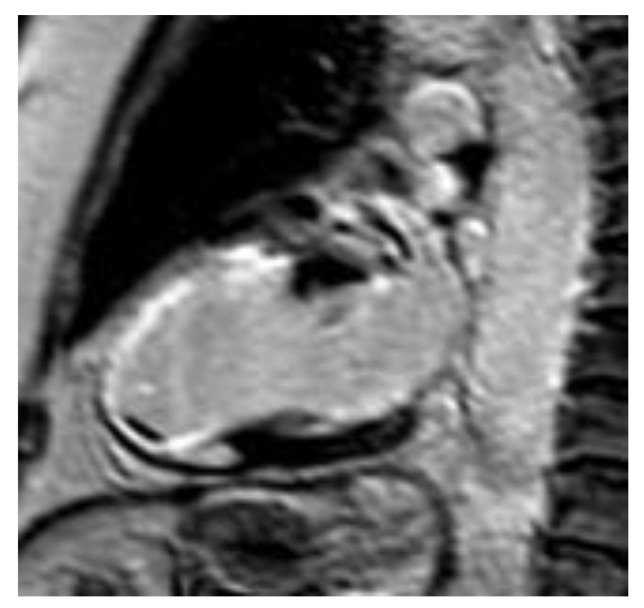

3.3. Hypertrophic Cardiomyopathy